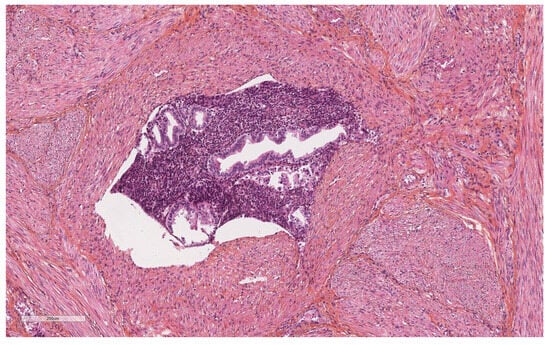

Artefacts in Hysterectomies with a Special Focus on Vascular Pseudoinvasion

| Vascular pseudoinvasion | |

| Present | 14 (23.7) |

| Absent | 46 (76.6) |